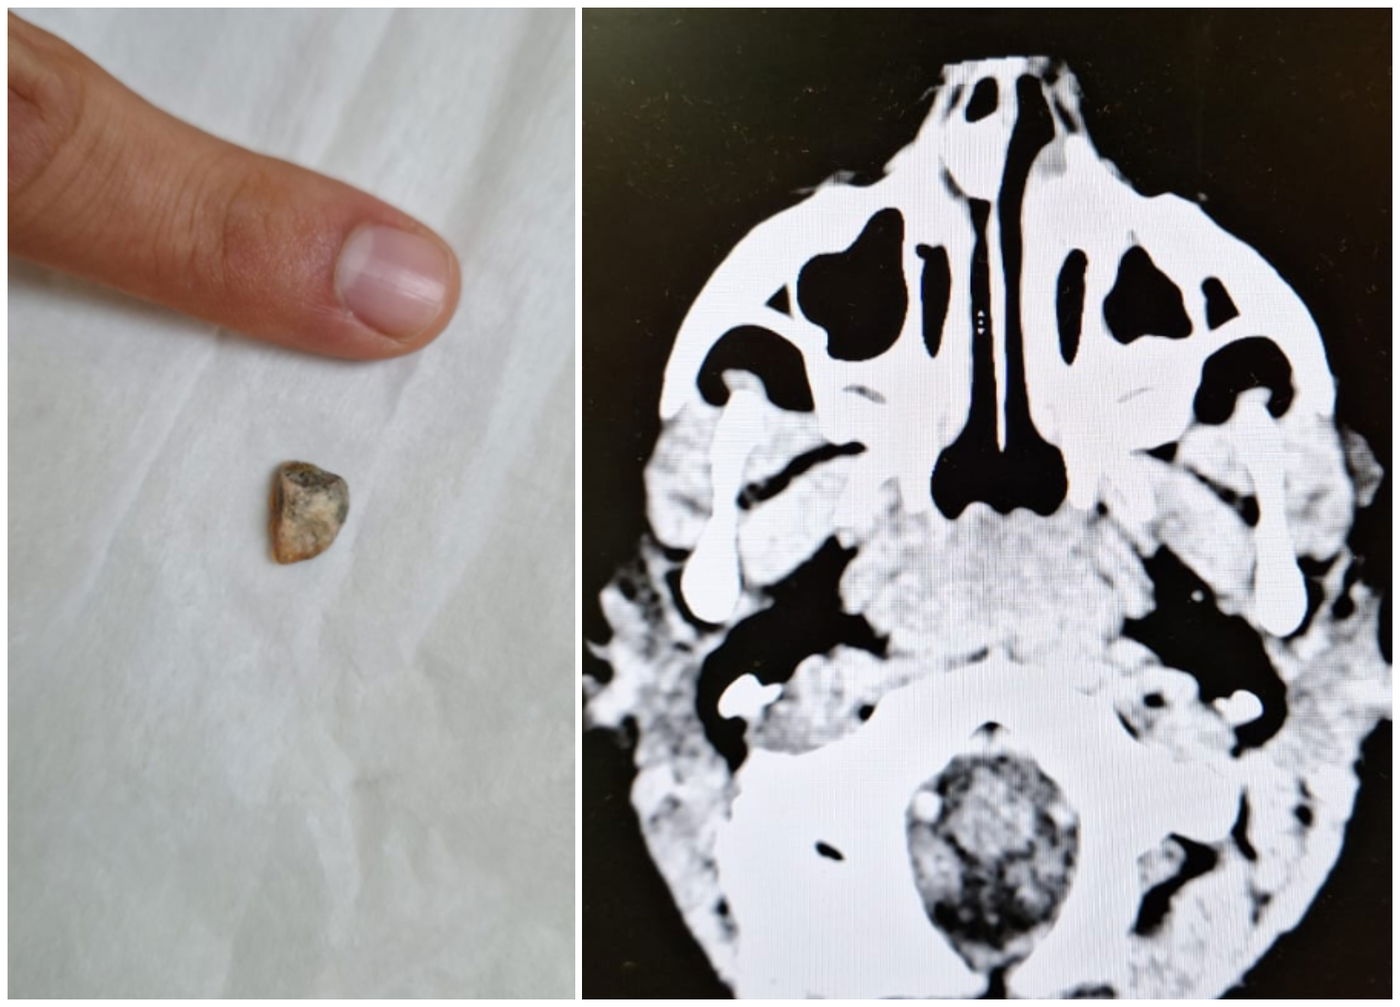

כחלק מתהליך הבירור בוצעה לילדה בדיקת ct על מנת להבין את מקור הכאב וההקאות. בצילום התגלתה הפתעה- אבן שיושבת כבר זמן מה בתוך אפה של הפעוטה.

בעקבות הסיטי הוצאה האבן מאפה של הילדה, ולשמחה התגלה כי הילדה חוותה כאבי ראש בגלל הנפילה ולא בגלל סיבה אחרת, והיא שוחררה לביתה ללא אבן באף ועם פחות כאבי ראש.

ד"ר אליחי ברלינר מהמרכז הרפואי שערי צדק שטיפל בילדה מספר: "א' הגיעה אלינו עם כאבי ראש חזקים והקאות, ומיד דאגו שתיכנס לבדיקת ct על מנת שנדע להבין מה מקור הבעיה. בסיטי חיכתה לנו הפתעה - אבן באף של א'. כשמטפלים בילדים מגלים אחת לכמה זמן כל מיני הפתעות בתוך גופם, אבל אבן באף עוד לא פגשנו. כמובן שהוצאנו את האבן ולשמחתנו א' שוחררה הביתה כשהיא במצב יותר טוב. אני קורא להורים לשים לב מה הילדים מכניסים לגוף".